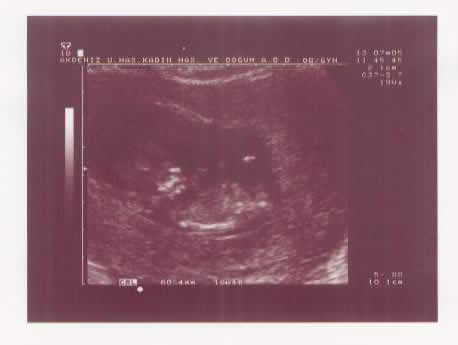

This is an ultrasound scan of Ender 12 weeks after conception.

At this stage we didn't know if he was a boy or a girl (I thought he looked like a potato), but we didn't care ... we were going to have a baby!

A ultrasound scan of Ender Patrick at 3 months.

Ender at 3 months into the pregnancy

We were so happy to see this ultrasound of a normal, healthy baby because at this time we had to make a decision whether or not to terminate the pregnancy with an abortion depending on the scan results.

Ender's ultra-sound scan looked normal at this stage.......